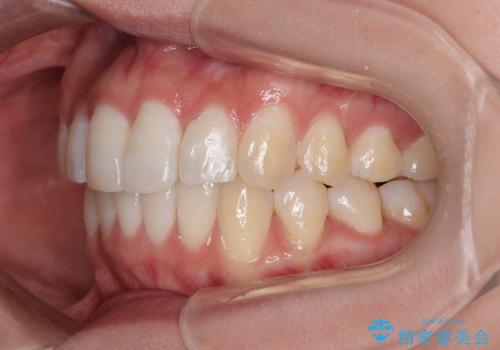

前歯のデコボコを治したい インビザライン矯正

- 上下前歯の叢生を気にして来院された患者様です。

インビザラインでの治療を希望されていて、デコボコの程度が中等度であり、安価なパッケージにて対応可能と判断されたため、インビザライン・モデレートを用いて矯正治療を行うこととしました。